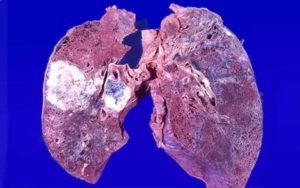

Низкодифференцированная аденокарцинома легких – одна из наиболее злокачественных видов опухолей. При развитии указанного патпроцесса наблюдается сильное разрастание стромы, и модификация тканей, образовавших тот или иной орган. Такие новообразования высокоактивны.

Уже на начальных стадиях своего генеза дают метастазы. Умеренно дифференцированная аденокарцинома легкого не имеет четко выраженных границ, состоит из атипичных клеток.

Бронхопульмональный железистый рак легких чаще всего выявляют в организме женщин. Опухоль высокоактивна, образует множественные метастазы. Этот вид канцера следует отличать от нейроэндокринного рака, альвеолярной аденомы, реактивных метапластических модификаций эпителия, склерозирующей гемангиомы, метастатических поражений, бронхоальвеолярной аденомы, атипичного карциноида.